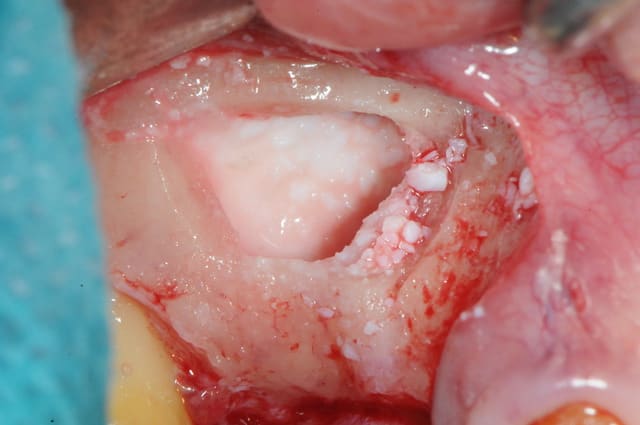

en attendant voici un des deux sinus de ce matin.

MP3 ( chez Pred) en comblement et ROG avec membrane et pins pour palier la forte concavité vestibulaire.